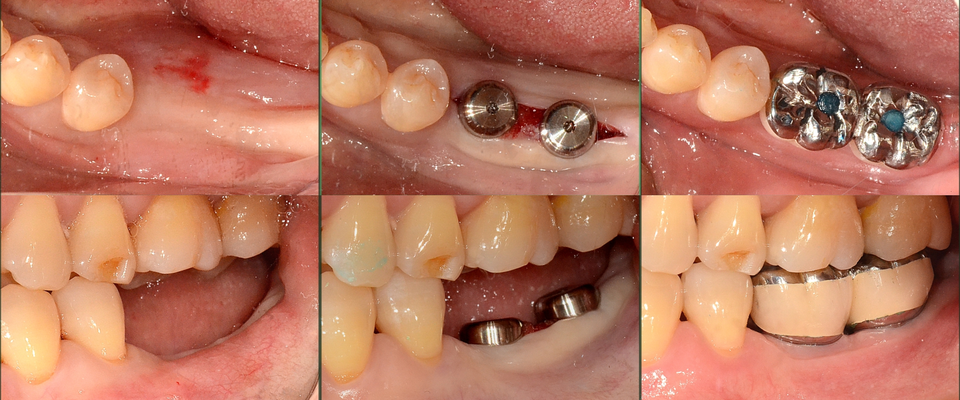

하지만, 추가적인 GBR 없이 Magic Fin Thread의 특성을 활용하여 좁은 골폭에서 최대 직경의 MagiCore를 식립할 수 있는 치료를 계획하고 한편, 부족한 부착치은은 최소 절개후 협측으로 확장하였다(그림3, 4).

이처럼 협설골폭이 위축된 경우에도 Magic GPS를 활용하는 식립 계획을 세울 수 있었고, 이를 통해 보다 정교한 임플란트 식립을 할 수 있었다.

술전에 장기간의 무치악으로 위축되어 있던 #36, 37협측치은은 최소한의 절개와 연조직에 손상을 주지 않는 Magic Drill의 특성으로 gingivalexpansion 하였다.

수술 후 점착된 결합조직과 접합상피를 인상채득과 보철체결과정 동안 전혀 분리시키지 않고 유지하는 Magic Cuff 의 장점으로 확장된 치은조직이 유지되고 개선되는 것을 확인할 수 있다(그림 9).